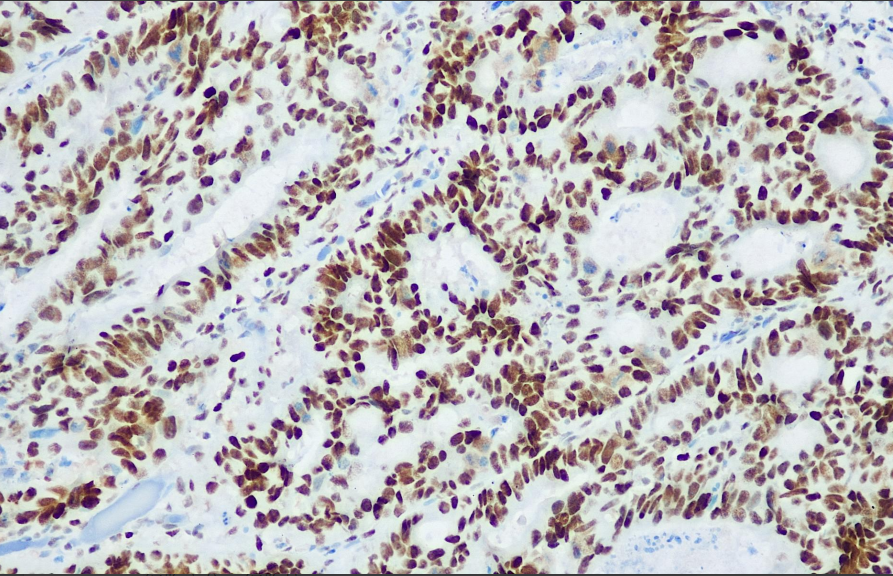

Cellular localization: nucleus

Positive control: Colorectal cancer

PMS2 antibody reagents can specifically bind to PMS2 molecular antigens. Immunohistochemistry kits containing PMS2 antibody reagents are suitable for the precise diagnosis of Lynch syndrome (HNPCC) and microsatellite instability (MSI-H) tumors.